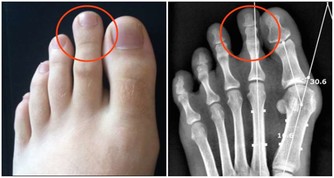

《黃帝內經》認為腎為“藏精之所,主骨生髓”,意即為生命的發動機,故古代醫家又稱腎為“先天之本”。腎藏精主生殖系統,如果生殖系統出現問題,比如說出現前列腺肥大,就說明腎的精氣不足了,要趕快補充精氣。老百姓常說“耳大有福”,背後的原理就是腎開竅於耳,腎氣充足則耳大飽滿、精力充沛,做事業自然拼勁十足、無往不利。曾國潘說“功名看氣宇,事業看精神”即是此意。經常耳鳴或者聽力下降的人,就是表明是腎氣不夠用了。什麼是腎主骨呢?中醫認為,人的骨骼強健與否,由腎精氣盈虧所決定。骨質疏鬆的人要補養腎的精氣,腎的精氣足了,骨骼就強健有力了。